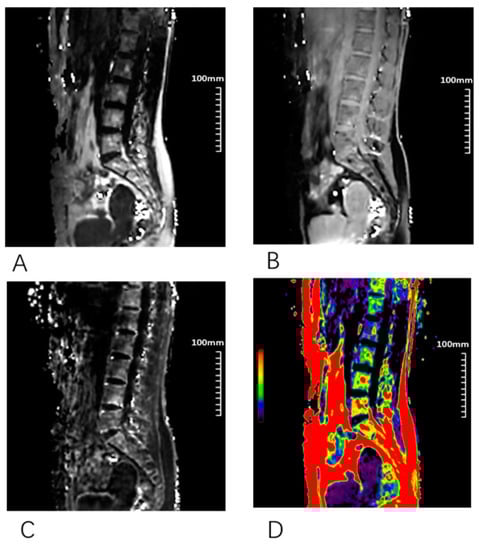

2.4. MR Examination

2.5. Image Analysis